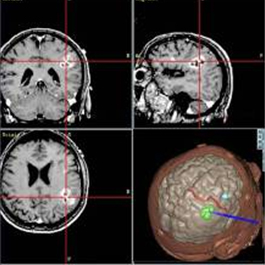

Un robot miniatura atraviesa el cerebro para extirpar tumores: Los investigadores apoyados por el NIBIB han desarrollado un Robot Neuroquirúrgico Intracraneal Mínimamente Invasivo (MINIR, por sus siglas en inglés) para la extracción de tumores cerebrales. Basado en lecciones aprendidas a partir del prototipo original, el MINIR-II mejorado está bajo el control directo del médico, utilizando imágenes obtenidas por sensores de resonancia magnética (RM) incrustados en el robot. Características adicionales integradas en el robot incluyen capacidades de irrigación, succión y extracción de tumores. El uso de la resonancia magnética permitirá el desarrollo de un sistema de rastreo y navegación que mejora la visión del cirujano, de las estructuras cercanas y distantes dentro del cerebro, para la localización y extracción precisa el tumor. El robot también será un dispositivo desechable, de un solo uso. Los investigadores esperan iniciar estudios clínicos con el MINIR-II en varios años.

La resonancia magnética guía herramientas quirúrgicas (negro) a un coágulo de sangre (color)